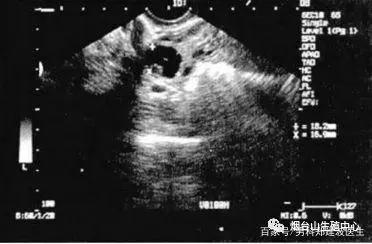

五、B超测量法

B超可以直接测量出卵泡的大小、形态和位置,同一月经周期内多次测量还可以观察到卵泡的整个生长发育、成熟、消失的过程,同时还可以观察子宫内膜的生长情况。但有时当我们测到一个成熟的卵泡,第二天可能就消失了,通常我们会认为排卵了,但是还有很小的几率,可能是卵泡意外破了,或萎缩不见了,并没有排卵。此时,将基础体温或孕酮和B超结果一起分析,才能得到准确答案。